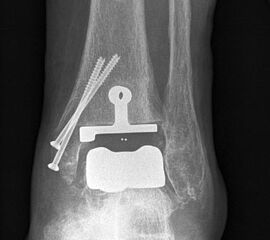

• Prothesenplanung anhand von Röntgenschablonen (Abb. 1 und 2).

Osteosynthese eines intraoperativ frakturierten medialen Malleolus mit perkutanen Schrauben.

Abbildung 19

Mögliche Ursachen können eine zu weit medial plazierte Tibiakomponente oder eine zu weit mediale, nicht nach lateral konvergierende Sägerichtung im Rahmen der ventrodorsalen distalen Tibiaresektion sein (Abb. 19).